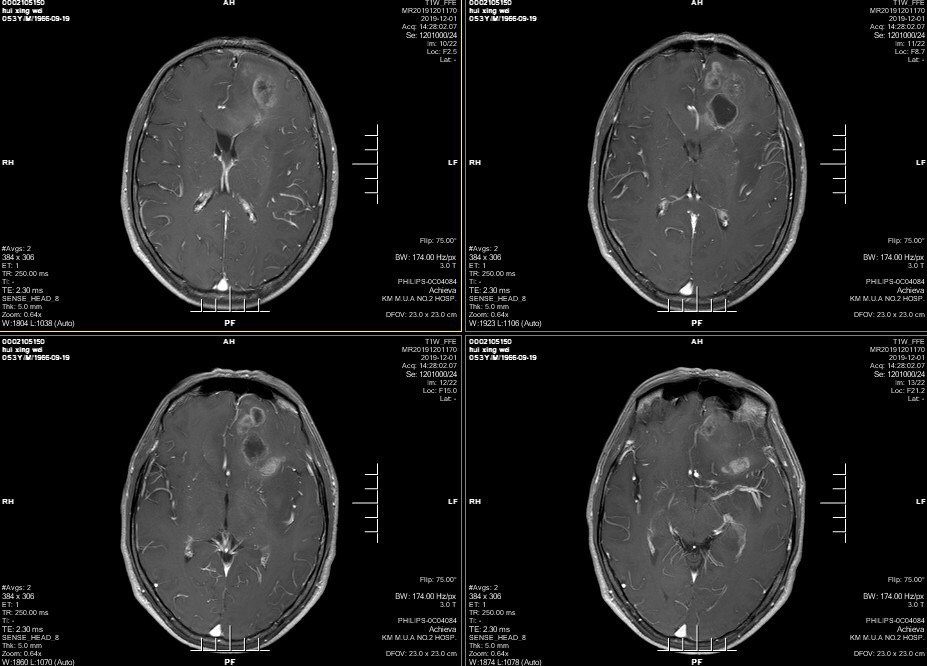

男性患者,53岁,主诉:反复头痛伴恶心一周,突发意识丧失一次。入院查体:神经体统无阳性体征。入院头颅MRI:左额叶胼胝体区囊实性占位,不均匀强化,考虑高级别胶质瘤;长程视频脑电监测提示左侧中央区、顶区、后颞区见中等量低-中-高波幅痫样放电。术前诊断:1.左额叶胼胝体区占位病变;2.继发性癫痫,入院给予降颅压及抗癫痫处理,积极完善术前准备后于2019年12月3日全麻下完成手术,术中行B超引导下切除肿瘤。术后患者无肢体功能及语言功能障碍,复查头颅核磁肿瘤全切,一周后出院开始放化疗治疗。

肿瘤为囊实性。

双侧大脑前动脉受肿瘤推挤。

增强后不均匀强化。